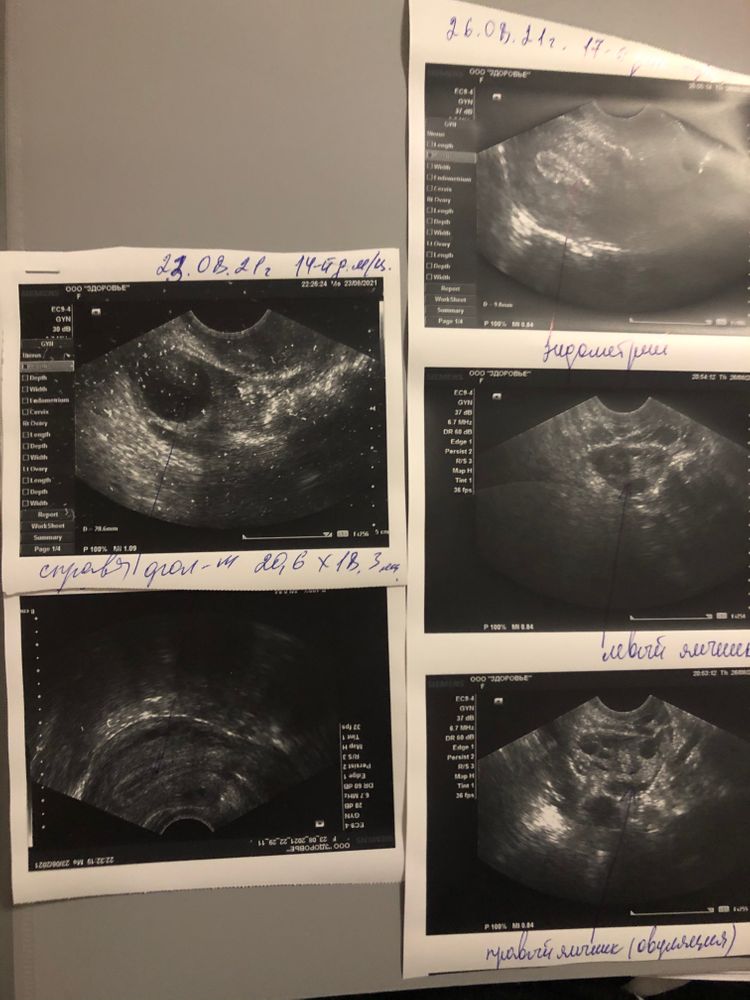

Karina, вроде да, ну говорила г подозрение на спкя Изображение Изображение